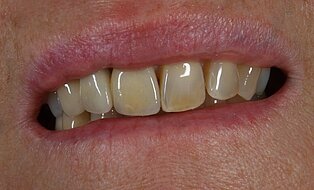

Patientenzufriedenheit